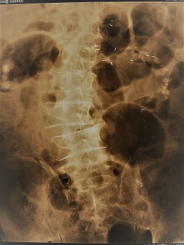

椎間板の消失 骨変形に伴う弯曲(1) (2) カルシウムの沈着

腰痛はもちろん、下肢のしびれ・筋力・感覚低下・麻痺・膝の変形などの他、排尿・排便障害に至ります。

これらのレントゲン写真のような人は程度に差はあれ、60代後半の人に多く見受けられている状態です。